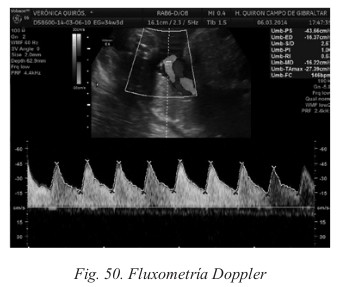

B. Fluxometría Doppler

El Doppler se basa en la emisión mediante un transductor de pulsos de ondas ultrasónicas a una determinada frecuencia, cuando estos pulsos alcanzan los hematíes, son reflejados con un cambio de frecuencia que podemos conocer en el transductor y convertir en voltajes (Fig. 50).

Es muy útil para la investigación de la circulación uteroplacentaria y sus alteraciones. Permite un estudio hemodinámico del feto y de la circulación uteroplacentaria, y completa el estudio biométrico y morfológico.